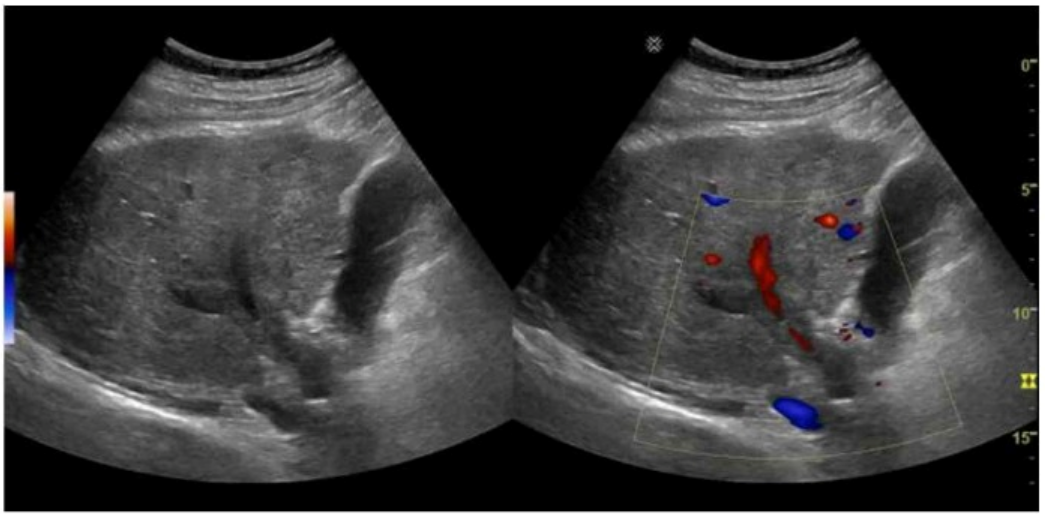

The sonographic images depict an acute thrombotic process involving the portal venous system. The absence of cavernous transformation in the setting of portal vein thrombus indicates that the process is acute. In chronic portal vein thrombosis, collateral vessels form in the porta hepatis to bypass the obstruction, a process known as cavernous transformation.

Sonographic features suggesting acute portal vein thrombosis:

Echogenic thrombus within the portal vein lumen

Absence of flow on color Doppler

No evidence of cavernous transformation (i.e., no serpiginous collateral vessels at porta hepatis)

Cavernous transformation is a hallmark of chronic portal vein thrombosis and takes weeks to months to develop. Therefore, its absence on ultrasound supports an acute diagnosis.